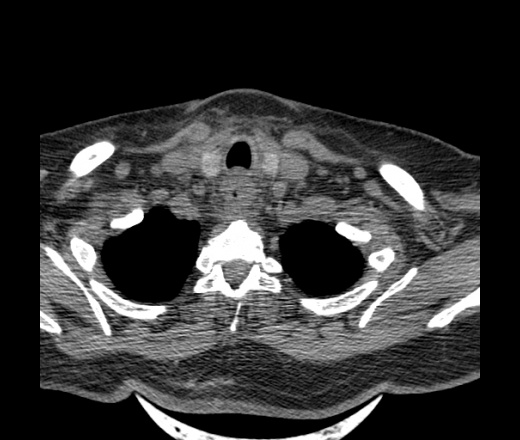

Женщина поступила в х/о спустя 4 дня после того как при употреблении карася подавилась костью.

Наличие газа в средостении на протяжении тел С2-С6 (медиастинальна эмфизема); рыбная кость на уровне тела С6.

При всем уважении, но говорить о медиастинальной эмфиземе, оценивая мягкие ткани шеи, как-то слишком резко. На мой взгляд, это ретрофарингеальное пространство.

Эвакуировали почти 100мл гноя. Но кость не смогли найти. Думаю что она даст дальнейшее ослоднение. Эндоскопически за черпалонадгортаной звязкой не смогли зайти в пищевод, все мягкие ткани отечные, просвет пищевода сдавлен. По всей видимости параэзофагеальная клетчака тоже задействована. Эмпиема, если ее можно так назвать, незнаю как правильно дошла до уровня яремной вырезки. Чем закончиться напишу. Ждем медиастинита.

Флегмона заглоточного пространства шеи, только операция, флегмоны вскрывают. Риск медиастинита.

Согласен с Вами; конечно, наличие газа в клетчатке ретрофарингеального пространства (затмение с опечаткой..). К сожалению, процесс "продвигается" к медиастиниту. Но почему никто, не отмечает наличие рыб. кости; или это для Всех очевидно?

Так вы уже отметили. Хотя ориентировал бы не скелетотопически, а на перстнечерпаловидный сустав.

Кость то мы сразу выявили, размеры где то 17*2мм, но ее так и не получается найти в этой каше